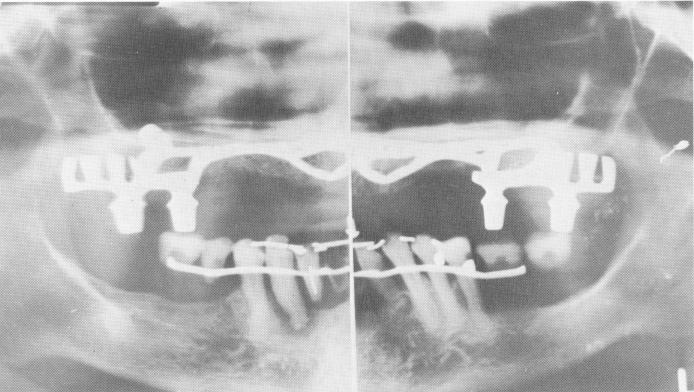

Fig. 11-186. The final Panorex. The mandibular arch was later restored.

2 Final Panorex after mandibular arch restoration